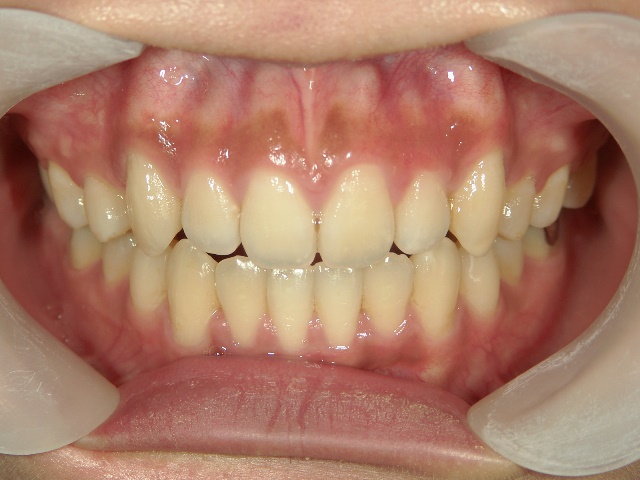

2年を少し過ぎたころには歯並びが良くなり、開咬もだいぶ改善されました。結婚式を予定していたため早期終了をさせていただきましたが、開咬が治ってハンバーガーをガブッと噛みきることができるようになって、とっても嬉しいです。式でもきれいな歯並びで、思いっきり笑うことができました。

出っ歯や八重歯などの歯並びの悪さばかりが気になっていましたが、開咬には前歯で物が噛みきれない、しゃべるときに息が漏れるなどの症状の他に、奥歯ばかりに負担がかかる為、歯の寿命を縮めてしまう可能性がありました。矯正で改善することができて本当によかっと思います。みなさんも歯並びで気になることがあったら、気軽に相談してみてくださいね。